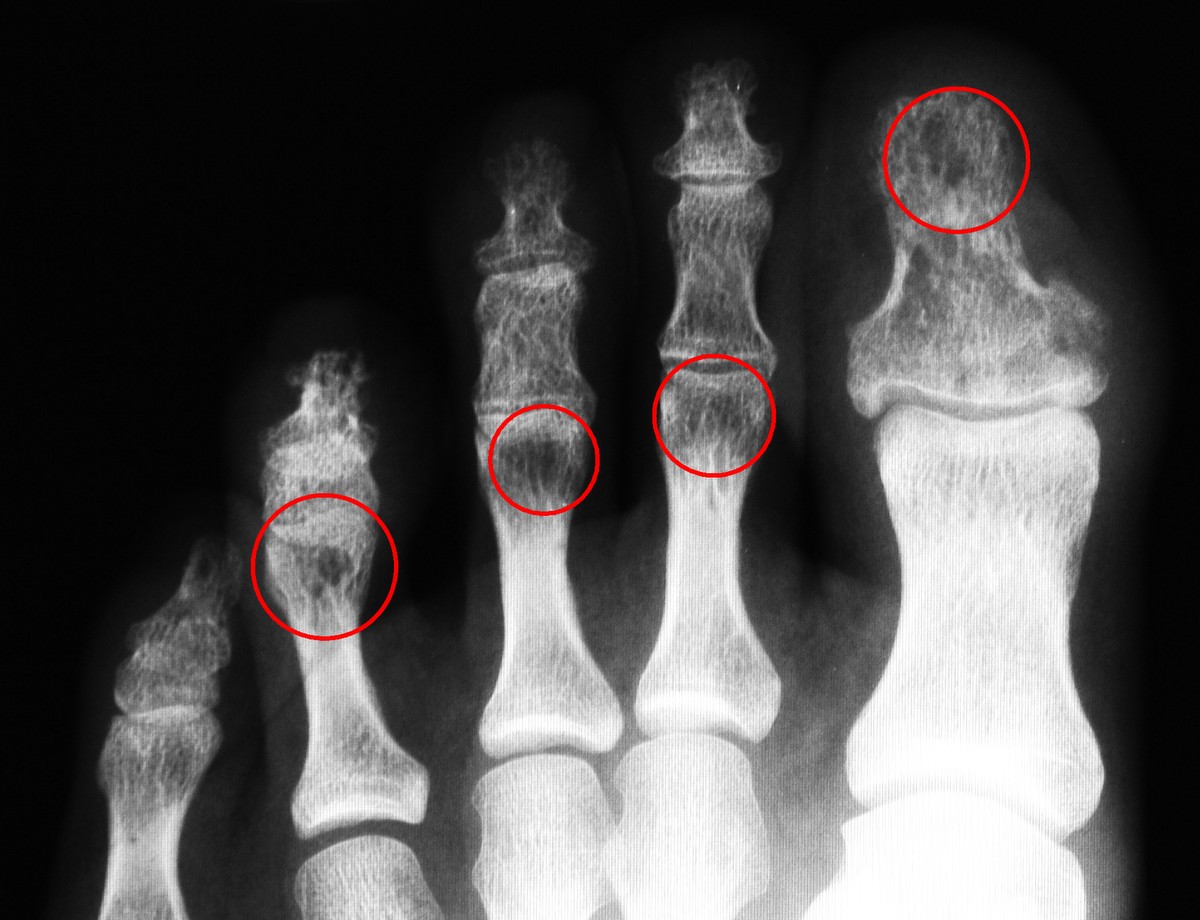

stattdessen zeige ich hier beispielhaft ein röntgen-bild des linken fußes:

hier versagt natürlich die auflösung einer standard-darstellung im webbrowser, dennoch sind als dunkle flecken die cysten (hohlräume) zu erkennen.

einige bereiche habe ich markiert.

auch die feine struktur eines normalen knochenaufbaus hat sich aufgelöst.